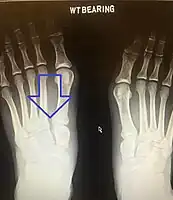

| An X-ray of a Lisfranc injury showing widening between the 1st and 2nd metatarsal base. | |

Lisfranc dislocation of the left foot due to lisfranc ligament rupture as seen on bilateral weight bearing radiographs.[1]